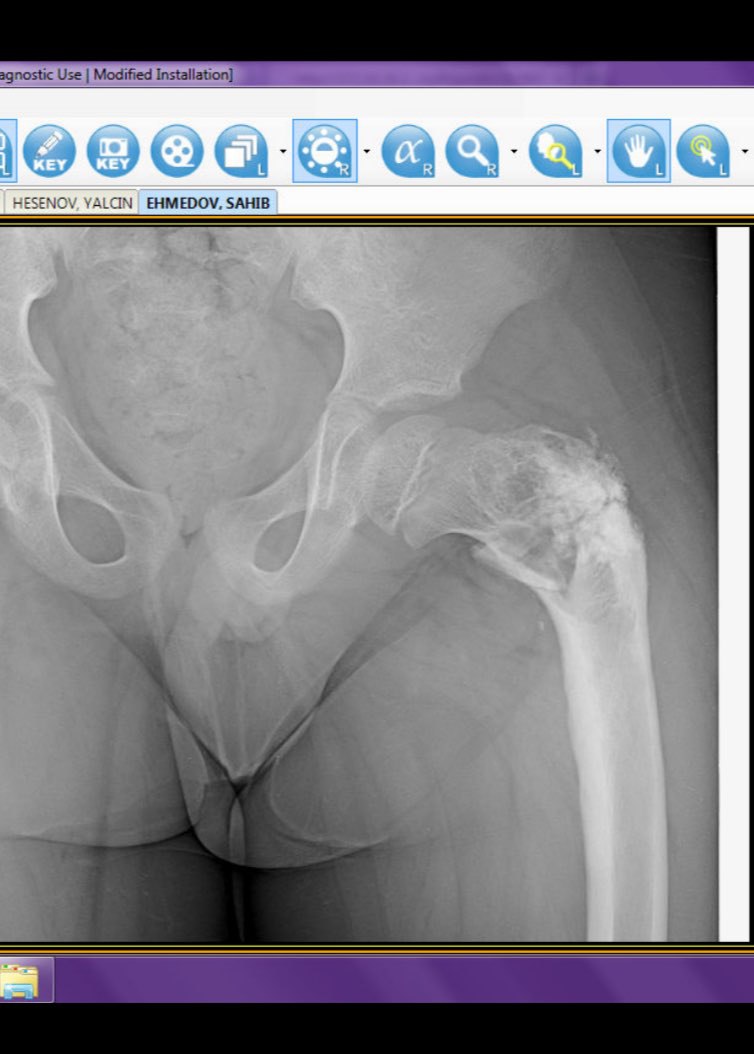

Коллеги всем привет. Тут была операция у ребенка 2 года назад, сейчас боли,  как описать этот перелом? Помогите плиз

Да есть перелом шейки аснования

Патологического не похоже?

Может патологик перелом

Поэтому анамнез нужно